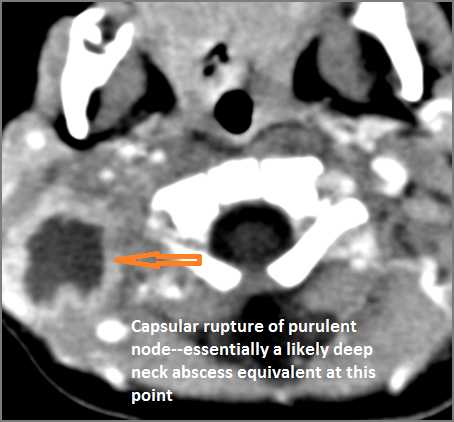

Cervical Lymph Nodes

If there is suppurative cervical adenopathy the purulent material outside the lymph node(s) capsule(s).